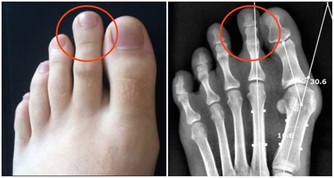

隱白穴:位於足大趾末節內側,距趾甲角0.1寸處。